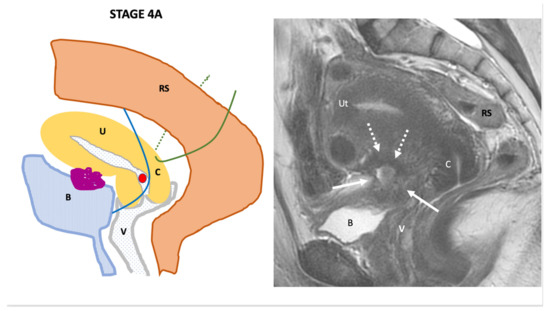

| Endo-Stage MRI | Location | Extent | Risk Stratification |

|---|---|---|---|

| Endo-Stage MRI 0 | Superficial endometriosis |

| Low |

| Endometriosis is strictly confined to the ovaries |

| ||

| Endo-Stage MRI I | Endometriosis is strictly confined to the retrocervical area |

| |

| Endo-Stage MRI II | Endometriosis invades beyond the retrocervical area, but not to the pelvic side-wall |

| Endo-Stage MRI III | Endometriosis extends to the pelvic side-wall and/or causes hydronephrosis or non-functioning kidney |

| Intermediate |

| Endo-Stage MRI IV | Endometriosis has involved the bladder or rectosigmoid colon |

| Endo-Stage MRI V | Multiple deep endometrioticlocations |

| High |